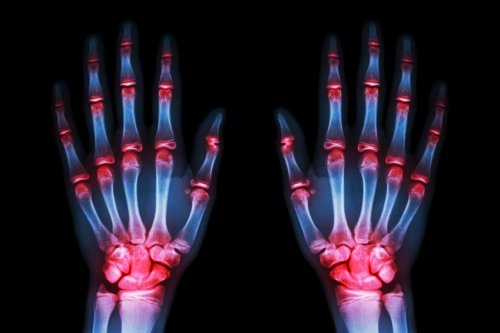

- Nivelrikko on kaikkein tavallisinta käsissä (70 %).

- Kuten tiedät, kun käymme lääkärissä apua saadaksemme, kyse on siitä että kipu on muuttunut jo sietämättömäksi. Kipu käsissä on nivelrikon edettyä tähän pisteeseen kauhea, kädet ovat tunnottomat öisin, ja niissä näkyy jo pieniä epämuodostumia.